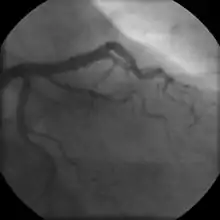

- Coronary angiography

Stable angina is the most common form of ischemic heart disease, and is associated with reduced quality of life and increased mortality. It is caused by epicardial coronary stenosis which results in reduced blood flow and oxygen supply to the myocardium.[71] Stable angina is characterized as short-term chest pain during physical exertion caused by an imbalance between myocardial oxygen supply and metabolic oxygen demand. Various forms of cardiac stress tests may be used to induce both symptoms and detect changes by way of electrocardiography (using an ECG), echocardiography (using ultrasound of the heart) or scintigraphy (using uptake of radionuclide by the heart muscle). If part of the heart seems to receive an insufficient blood supply, coronary angiography may be used to identify stenosis of the coronary arteries and suitability for angioplasty or bypass surgery.[72]